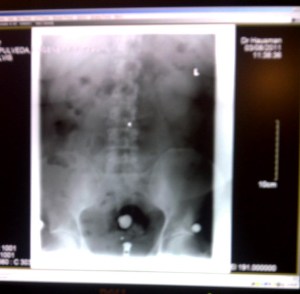

Xrays revealed my spine is bent a bit to the left, which reconciles with my muscle spasms. When they occur my right leg becomes about 1 – 2 inches shorter. I asked if chicken or egg – whether spine driven or muscle driven, the doctor thinks spine driven and correctable. Best guess is 6 to 9 treatments including pressure point massage. So, I’m going down this path. New for me. Science or art?